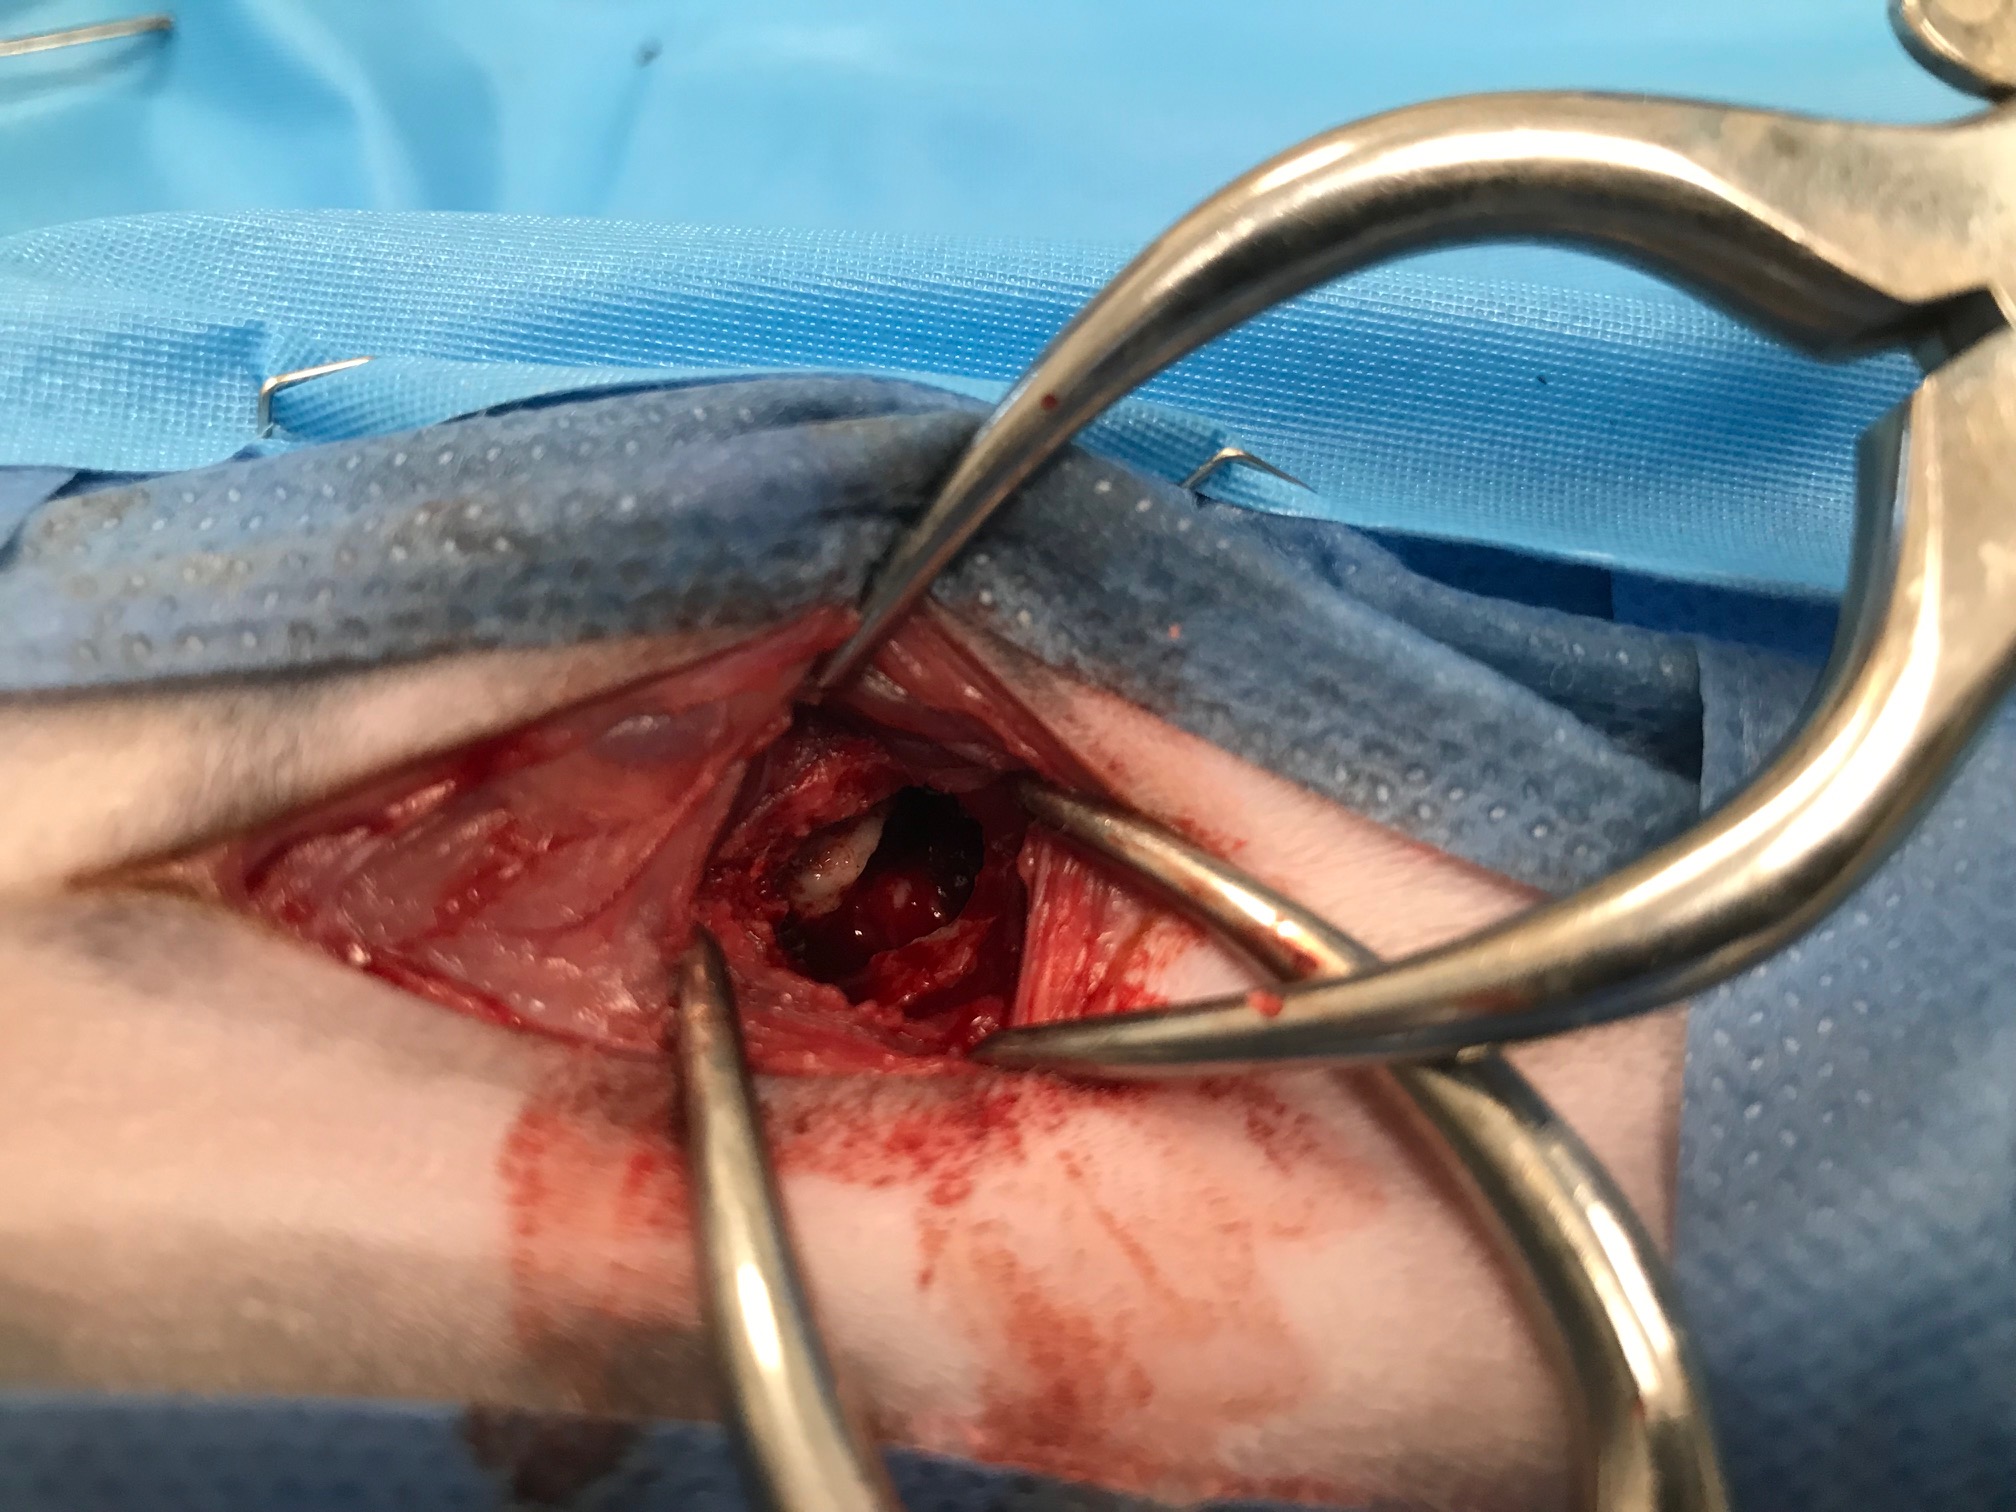

-Les étapes de la TECALBO en photos et vidéos

TECALBO : comment la réaliser en pratique.